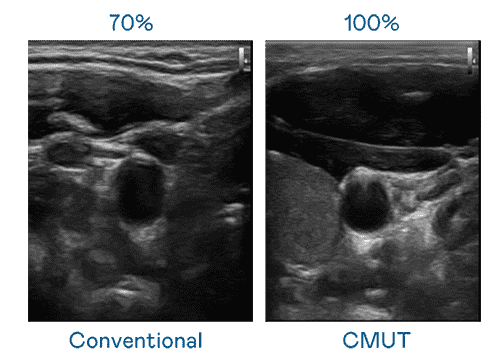

CMUT 技术是一种用电容式微机电元件来产生超音波讯号的技术。。与传统 PZT 压电式技术相比,,,,CMUT 频宽增加 30%,,更宽频的超音波讯号让影像解析度大幅提升,,,,是实现高影像品质医疗超音波扫描、、、促进精准医疗发展的关键技术。。

超音波影像的解析度高低,,,首先取决于探头能发出的讯号频宽。。918.COM CMUT 可提供高清晰的超音波讯号,,,,提供高频宽、、、高灵敏度、、、、影像纹理细节更高的超音波影像,,,,协助医护人员缩短影像判读时间及利用精准的医疗影像进行诊断。。